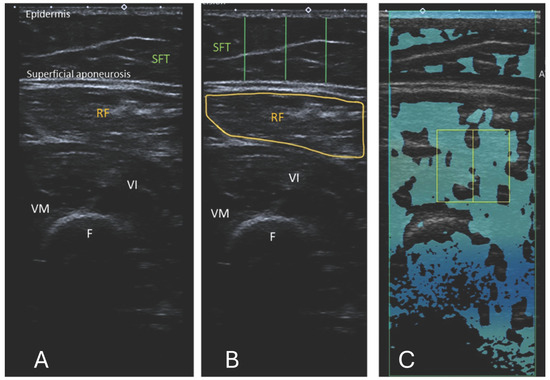

Comparison of Attenuation Imaging in the Rectus Femoris and Biceps Brachii Muscles with Multiecho Dixon-Based Fat Quantification and Ultrasound Echo Intensity

by Sophia Zoller, Karolina Pawlus, Catherine Paverd, Thomas Frauenfelder, Florian A. Huber and Alexander Martin

Diagnostics 2025, 15(24), 3239; https://doi.org/10.3390/diagnostics15243239 - 18 Dec 2025

Background/Objectives: Sarcopenia, an underdiagnosed musculoskeletal disorder, is a serious cause of disability, poor quality of life, and healthcare costs in an increasingly elderly population. This study aimed to examine an ultrasound (US)-based, inexpensive, simple, and reproducible alternative to magnetic resonance imaging (MRI) [...] Read more.

Background/Objectives: Sarcopenia, an underdiagnosed musculoskeletal disorder, is a serious cause of disability, poor quality of life, and healthcare costs in an increasingly elderly population. This study aimed to examine an ultrasound (US)-based, inexpensive, simple, and reproducible alternative to magnetic resonance imaging (MRI) for assessing muscle quality. A study compared Dixon MR fat fraction with US attenuation imaging (ATI) and echo intensity (EI) in the rectus femoris (RF) and biceps brachii (BB). Methods: The US images were acquired from 34 participants who had previously received a whole-body MRI. The ATI measurements were carried out using a linear array on a Canon Aplio i800 scanner. The measurements of EI were assessed by manually tracing the cross-sectional border of the right RF and BB muscles. Corresponding T1-weighted Dixon VIBE-based fat and water images were required for the MRI fat fraction percentage (MR %FF) measurements. Results: Using Pearsons correlation coefficient, a good correlation was found between MR %FF and EI measurements. The results between operators’ measurements showed a strong correlation and were highly repeatable. Attenuation imaging revealed no correlation with MR %FF or EI. Conclusions: Echo intensity offers a low-cost, non-invasive, and widely accessible US-based imaging modality for screening patients at risk for sarcopenia. No correlation was found between the ATI and MR %FF or between the ATI and EI. Further adapted protocols and software adjustments are needed so that ATI has the potential to prove itself as an additional US-based method for assessing fat infiltration in muscles. Full article